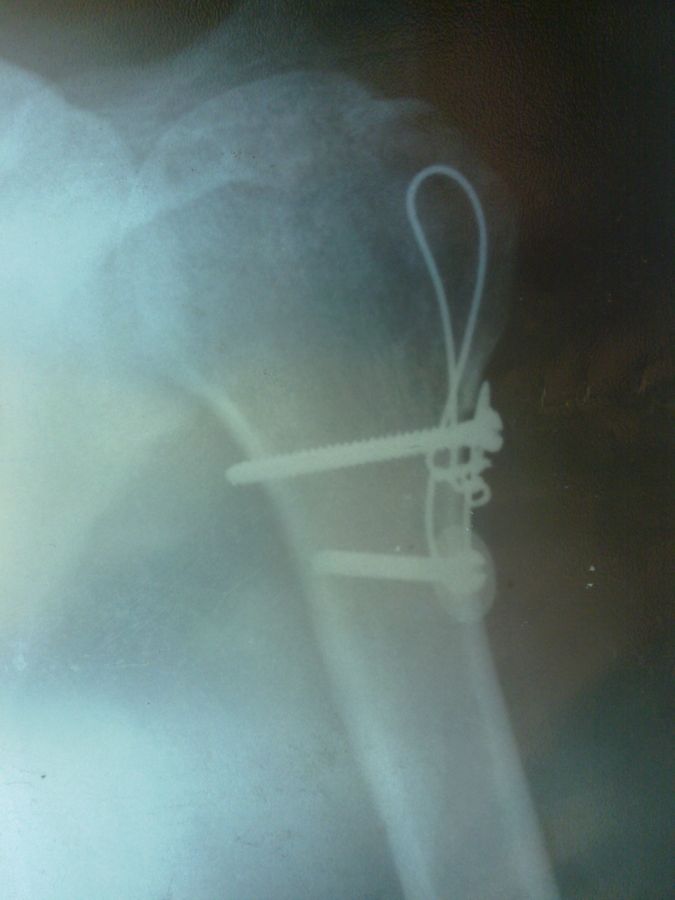

А мне намедни болты из плеча вырезали. Очень рад.

Хоть они меня и не беспокоили, но всё равно было не приятно таскать в себе железо.

STARGAZER, а чё это там за проволока?

Шплинт?

Гидр, не, не шплинт. Вот этой петлёй, которая сверху проволока давила на кусок кости который врачи отрезали от бедра и выточили из него недостающую часть для плечевой кости т.к. родная часть развалилась к чертям свинячим, а болты создавали силу давления. Там на снимке если присмотреться, то видно что кусочек большого бугра как бы не родной, типа приклееный. Короче объяснил как мог. Вот такие чудеса творят наши травматологи В.П. Лучинин и М.В. Гордин. Большое им спасибо, доктора от Бога.